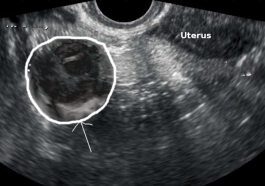

abscess

Tubo-Ovarian Abscess: A Serious Female Reproductive Infection

Light House Denver - Tubo-ovarian abscess (TOA) is a serious condition caused by an infection that forms a pus-filled mass…